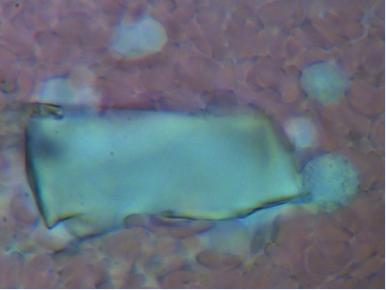

1.CHOLESTEROL

Podczas badania często stwierdzana jest obecność kryształków cholesterolu. W zależności od ich wielkości możemy określić zagrożenie rozwoju miażdżycy, wystąpienia zawału czy zakrzepu. Nawet jeżeli wartości biochemiczne mieszczą się w normie to przede wszystkim wielkość a w mniejszym stopniu ilość blach cholesterolowych zwiększa ryzyko wystąpienia choroby.

Powiększenie 1600x - aby wykonać zdjęcie całej blachy trzeba było wykonać cztery zdjęcia.